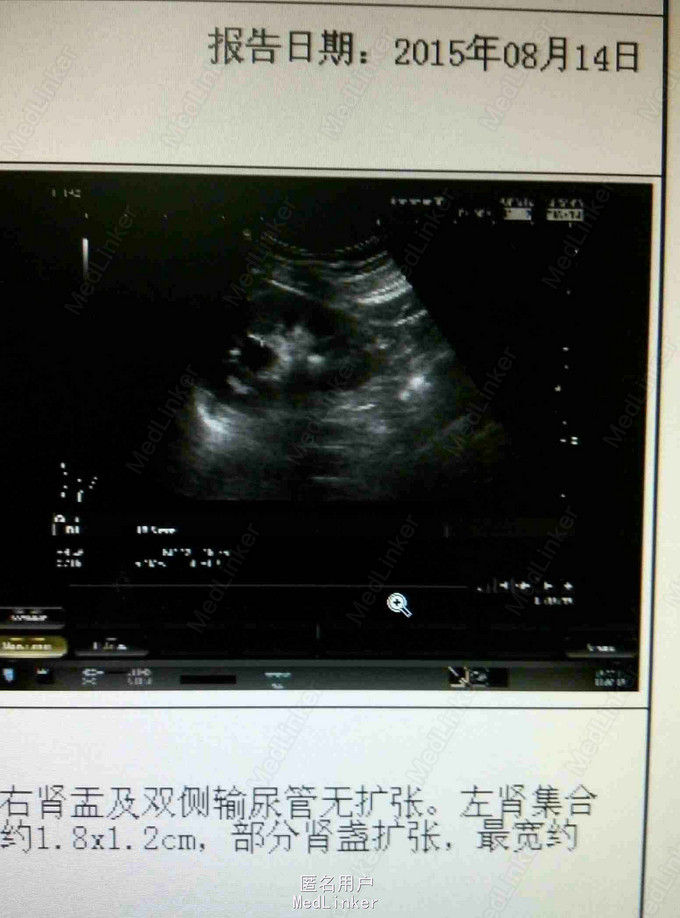

左肾结石一例

男,60岁。左腰不适二周。二周前自觉左腰部不适,无肉眼血尿及腰背绞痛。

左肾区有叩痛。尿中白细胞20/hp。

左肾结石,行经皮肾镜取石术。术后效果良好。